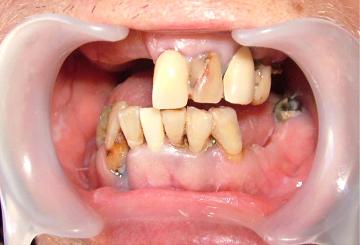

煙草は吸わない,酒も殆ど飲まない...なのに急に歯が溶け出して,歯の真ん中に穴が空くようになってしまった....これは間違いなく歯周病の「大病になる前のシグナル」である....ヘルプミー!...死にたくない...なに一つ楽しい事が無かったというのに...自分の人生は,なんだったんだ...今の生活を変えたい...いや変えなければ「大病」になる可能性があり,命に繋がってしまう...(苦笑)歯周病は,様々な大病病気を引き起こす前兆....助けてくれ!自分は,まだ死にたくない...最近,やたらと「頭痛=偏頭痛」が頻繁に起こる...糖尿病っていったって,急に直ぐ,そんな短期間ではならない筈だが...心臓病か,心筋梗塞か...